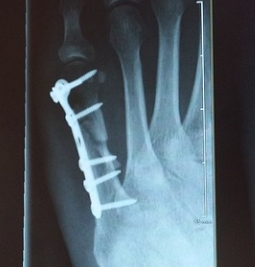

2. 외과 골절

발 관절이 강하게 바깥쪽으로 비틀어지게 되면 거골에 밀려 외과골절이 발생할 수 있고, 이는 나선형으로 꺾이는 경우가 많습니다. 뼈가 어긋남이 없다면 깁스등의 보존적 치료가 가능하며, 어긋남이 심하다면 플레이트와 나사등을 이용하여 고정하는 수술을 할 가능성이 있습니다.